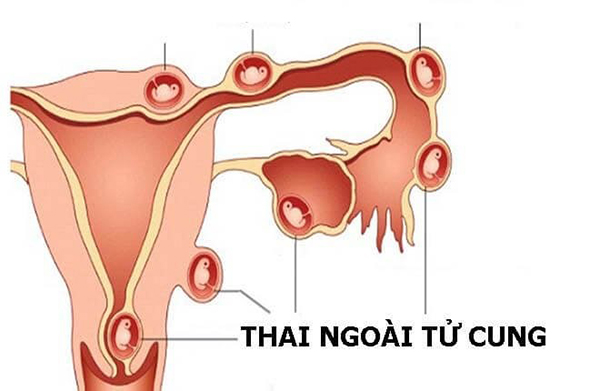

Nếu như bình thường thì sau khi thụ thai, trứng sẽ làm tổ ở bên trong tử cung và phát triển. Khi mang thai ngoài tử cung, trứng và tinh trùng thụ tinh nhưng lại làm tổ ở bên ngoài tử cung, ngoài buồng trứng, ổ phúc mạc hoặc ổ bụng… Trong đó, thai ở vòi tử cung là phổ biến hơn cả.

Khi ở bên ngoài tử cung, túi thai sẽ không được bảo bọc bởi buồng tử cung và có nguy cơ bị vỡ ra. Khi đó, máu từ túi thai có thể tràn vào ổ bụng và gây nguy hiểm cho sản phụ. Vậy có thai ngoài tử cung có sinh được không?